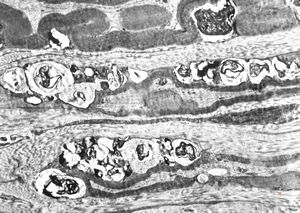

n. suralis - hypertrophic demyelinizing neuropathytoluidine-blue-stained semithin section

M, | hypertrophic (onion bulb) neuropathy accompanyingmultiple sclerosis

F,23y. | - n.suralis- hypertrophic demyelinizing neuropathy (onion bulbs)